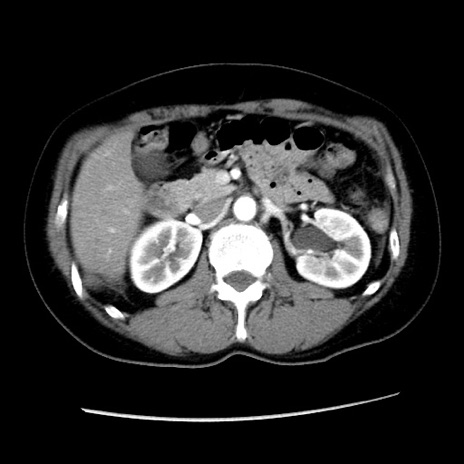

矢状断像